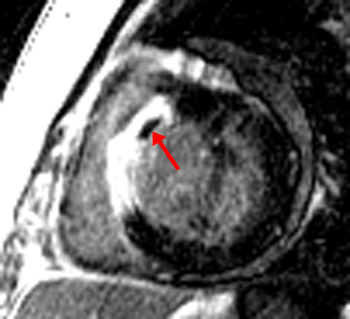

Answer: C. Aortic regurgitation and stenosis. There is both a stenotic jet which extends from the aortic valve into the ascending aorta during systole (arrow) as well as a smaller regurgitant jet extending from the aortic valve into the LV during diastole (arrowhead). Notice how there is minimal opening of the valve leaflets during systole, resulting in aortic stenosis. The right ventricle is not hypertrophied. With a ventricular septal defect, flow would be between the ventricles, which is not seen in this case. The severity of regurgitation or stenosis can be determined by the amount of signal void. Cardiac MRI has 98% sensitivity and 95% specificity for identification of aortic and mitral regurgitation. Higgins CB, Byrd BF, Stark D, et al. Diagnostic accuracy and estimation of the severity of valvular regurgitation from the signal void on cine magnetic resonance imaging. Am Heart J 1989; 118: 760-767.2) This inversion recovery sequence was taken 10 minutes after the administration of IV gadolinium. Which of the following entities does it show? ![]() Answer: B. DHE consistent with myocarditis. The image shows DHE (arrow) along the inferolateral wall of the left ventricle epicardium. The subendocardium is normal in this region. This finding is consistent with myocarditis as opposed to myocardial infarction in which DHE always involves at least the subendocardium. The structure within the left ventricular cavity is a normal papillary muscle seen in cross-section, not a thrombus or tumor. Laissy JP, Hyarfil F, Feldman LH, et al. Differentiating acute myocardial infarction from myocarditis: diagnostic value of early- and delayed- perfusion cardiac MR imaging. Radiology 2005; 237 (1):75-82.3) This horizontal long axis SSFP demonstrates which of the following entities? Answer: A. Apical septum wall motion abnormality. This cine shows a localized abnormality of the apical septum (arrow). The myocardium in this area does not thicken as much as the surrounding myocardium. When necessary, wall thickening can be quantified to assess region wall motion abnormalities. The remainder of the left ventricle functions normally, so global systolic of diastolic function is not present. Azhari H, Sideman S, Weiss JL, et al. Three-dimensional mapping of acute ischemic regions using MRI: wall thickening versus motion analysis. Am J Physiol 1990; 259:H1492-503.4) What are the primary physiologic consequences of the entity in the image shown below? ![]() Answer: C. Restricted diastolic filling and increase in venous pressures. The figures shown above are T1-weighted and T1-weighted with fat saturation images. The images show a pericardium that is thicker than 3 mm (arrows). This finding is consistent with constricted pericarditis in the appropriate clinical setting. Axel L. Assessment of pericardial disease by magnetic resonance and computed tomography. Journal of Magnetic Resonance Imaging 2004; 19(6):816-26.5) The cine below shows findings which are characteristic of which of the following? Answer: C. Arrhythmogenic right ventricular cardiomyopathy. The above cine shows a heart with marked RV dysfunction (arrow) out of proportion to the LV. The other entities listed would be expected to affect primarily the LV. Bluemke DA, Krupinski EA, Ovitt T, et al. MR Imaging of arrhythmogenic right ventricular cardiomyopathy: morphologic findings and interobserver reliability. Cardiology 2003; 99(3): 153-62.6) The gradient echo cine below shows what congenital abnormality? Answer: A. Atrial septal defect. There is a clear defect (arrow) in the superior aspect of the interatrial septum between the right and left atria. None of the other abnormalities are seen in this image. Wang ZJ, Reddy GP, Gotway MB, Yeh BM, Higgins CB. Cardiovascular shunts: MRI imaging evaluation. Radiographics 2003;23 Spec No:S181-94.7) This spin echo image shows what aortic abnormality? ![]() Answer: D. Aortic coarctation. This image shows an irregular narrowing at the aortic isthmus just distal to the left subclavian (arrow). MRI is especially useful in assessing the aorta after coarctation repair to assess for restenosis and the degree of collateralization utilizing VENC imaging. Kellenberger CJ, Yoo S, Valsangiacomo Buchel ER. Cardiovascular MR Imaginging in Neonates and Infants with Congenital Heart Disease. Radiographics 2007;27:5-18.8) Which of the following is shown in the IR image below acquired 10 minutes following infusion of gadolinium contrast agent? ![]() Answer: B. Subendocardial infarct. This image shows delayed hyperenhancement of the inferoseptal, inferolateral wall, and lateral LV wall. The DHE involves the subendocardium (arrow) which is suggestive of infarction, as opposed to the mid myocardial or epicardial location in myocarditis. The DHE does not involve the entire wall however, so it is a subendocardial as opposed to transmural infarct. A ventricular aneurysm would show a focal bulge of ventricular wall. Wu E, Judd RM, Vargas JD, Klocke FJ, Bonow RO, Kim RJ. Visualization of presence, location, and transmural extent of healed Q-wave and non-Q-wave myocardial infarction. Lancet 2001; 357 (9249): 21-8.9) The cine image below uses a technique specialized to determine what entity? Answer: C. Myocardial strain. This cine image uses a special modulation of magnetization to produce tag lines that move with the myocardium. The degree of deformation of the squares is used to calculate myocardial strain, which gives an accurate (sensitivity 92%, specificity 99%) quantitative assessment of myocardial function. A series of non-tagged short axis images can be used to measure ejection fraction, end-systolic volume and myocardial mass. Myocardial perfusion imaging uses gadolinium and adenosine. Gotte MJW, van Rossum AC, Twisk JWR, et al., Quantification of regional contractile function after infarction: strain analysis superior to wall thickening analysis in discriminating infarct from remote myocardium. J Am Coll Cardiol 2001; 37: 808-817.10) Which congenital cardiac anomaly is shown on the gradient echo cine below? Answer: A. Ebstein’s anomaly. In Ebstein's anomaly, the septal and posterior leaflets of the tricuspid valve (arrows) are displaced apically resulting in atrialization of the base of the right ventricle. The tricuspid annulus, however, is normally positioned between the right atrium and ventricle. The atrialized portion of the RV is thinned and prone to aneurysmal dilation. There is no connection between the two sides of the heart that would suggest a ASD or VSD. None of the findings of Tetralogy of Fallot are present. The pulmonic valve and aortic arch are not visualized in this slice. Choi YH, Park JH, Choe YH, et al. MR imaging of Ebstein’s anomaly of the triuspid valve. Am J Roentgenol 1994; 163:539-43.11) Below are pre and post gadolinium SSFP images. What abnormality do they show? ![]() Answer: D. Thrombus. The mass in the LV does not enhnance on post-contrast imaging, which is consistent with a thrombus. Thrombi form in regions of akinesis, typically due to myocardial infarctions. Microvascular obstruction is a process which involves the myocardium. Myxomas and metastatic disease typically have a heterogenous appearance and enhance. Papillary muscles enhance with myocardium. Friedrich MG. Magnetic resonance imaging in cardiomyopathies. J Cardiovasc Magn Reson 2000;2:67-82.12) Which of the following is seen on the gradient echo cine below? Answer: B. Pericardial effusion causing cardiac tamponade. There is a large amount of fluid in the pericardial sac (arrows). This fluid is physiologically significant because the contractile function of the heart is compromised and there is diastolic collapse of multiple chambers. The fluid is within the pericardium surrounding the heart, thus excluding pericardial cyst. The pericardium is not thickened, essentially excluding constrictive pericarditis. This diagnosis is usually made with echocardiography. Bilateral pleural effusions are also present. Wang ZJ, Reddy GP, Gotway MB, Yeh BM, Hetts SW, Higgins CB. CT and MR imaging of pericardial disease. Radiographics 2003; 23: S167-80.13) What abnormality is seen in this cine? ![]() Answer: C. Delayed hyperenhancement of hypertrophic cardiomyopathy. The DHE vertical long axis image demonstrates regional hypertrophy of the myocardium in the anterior wall (arrows) which is consistent with hypertrophic cardiomyopathy. There is also subepicardial and mid-myocardial delayed enhancement in the region of the hypertrophy which is due to fibrosis. Rickers C, Willke NM, Jero-Herlold M, et al. Utility of cardiac magnetic resonance imaging in the diagnosis of hypertrophic cardiomyopathy. Circulation 2005; 112(6):855-61.14) What abnormality is seen on the SSFP vertical long axis cine seen below? Answer: A. Myxoma. This cine shows a myxoma (arrow) within the left atrium that is partially prolapsing through the mitral valve. Myxomas are most often located in the left atrium, often pedunculated, and commonly attached to the interatrial septum. When large, they can obstruct the mitral valve and cause symptoms of mitral stenosis. Myxomas are well encapsulated unlike angiosarcomas which are a malignant tumor and are very invasive. A lipoma should have the same signal as subcutaneous fat, therefore it would be much brighter than this mass. This would be an unusual location for an intracardial thrombus, which typically form in areas of minimal motion. Sparrow PJ, Kurian JB, Jones TR, Sivananthan MU. MR Imaging of cardiac tumors. Radiographics 2005; 25(5): 1255-76.15) Below are perfusion images of basal, mid, and apical slices along with a delayed hyperenhancement image (bottom) aligned with the mid slice. The resting images are displayed on the top left with the Adenosine images displayed in the top right. What abnormality is seen in these images?